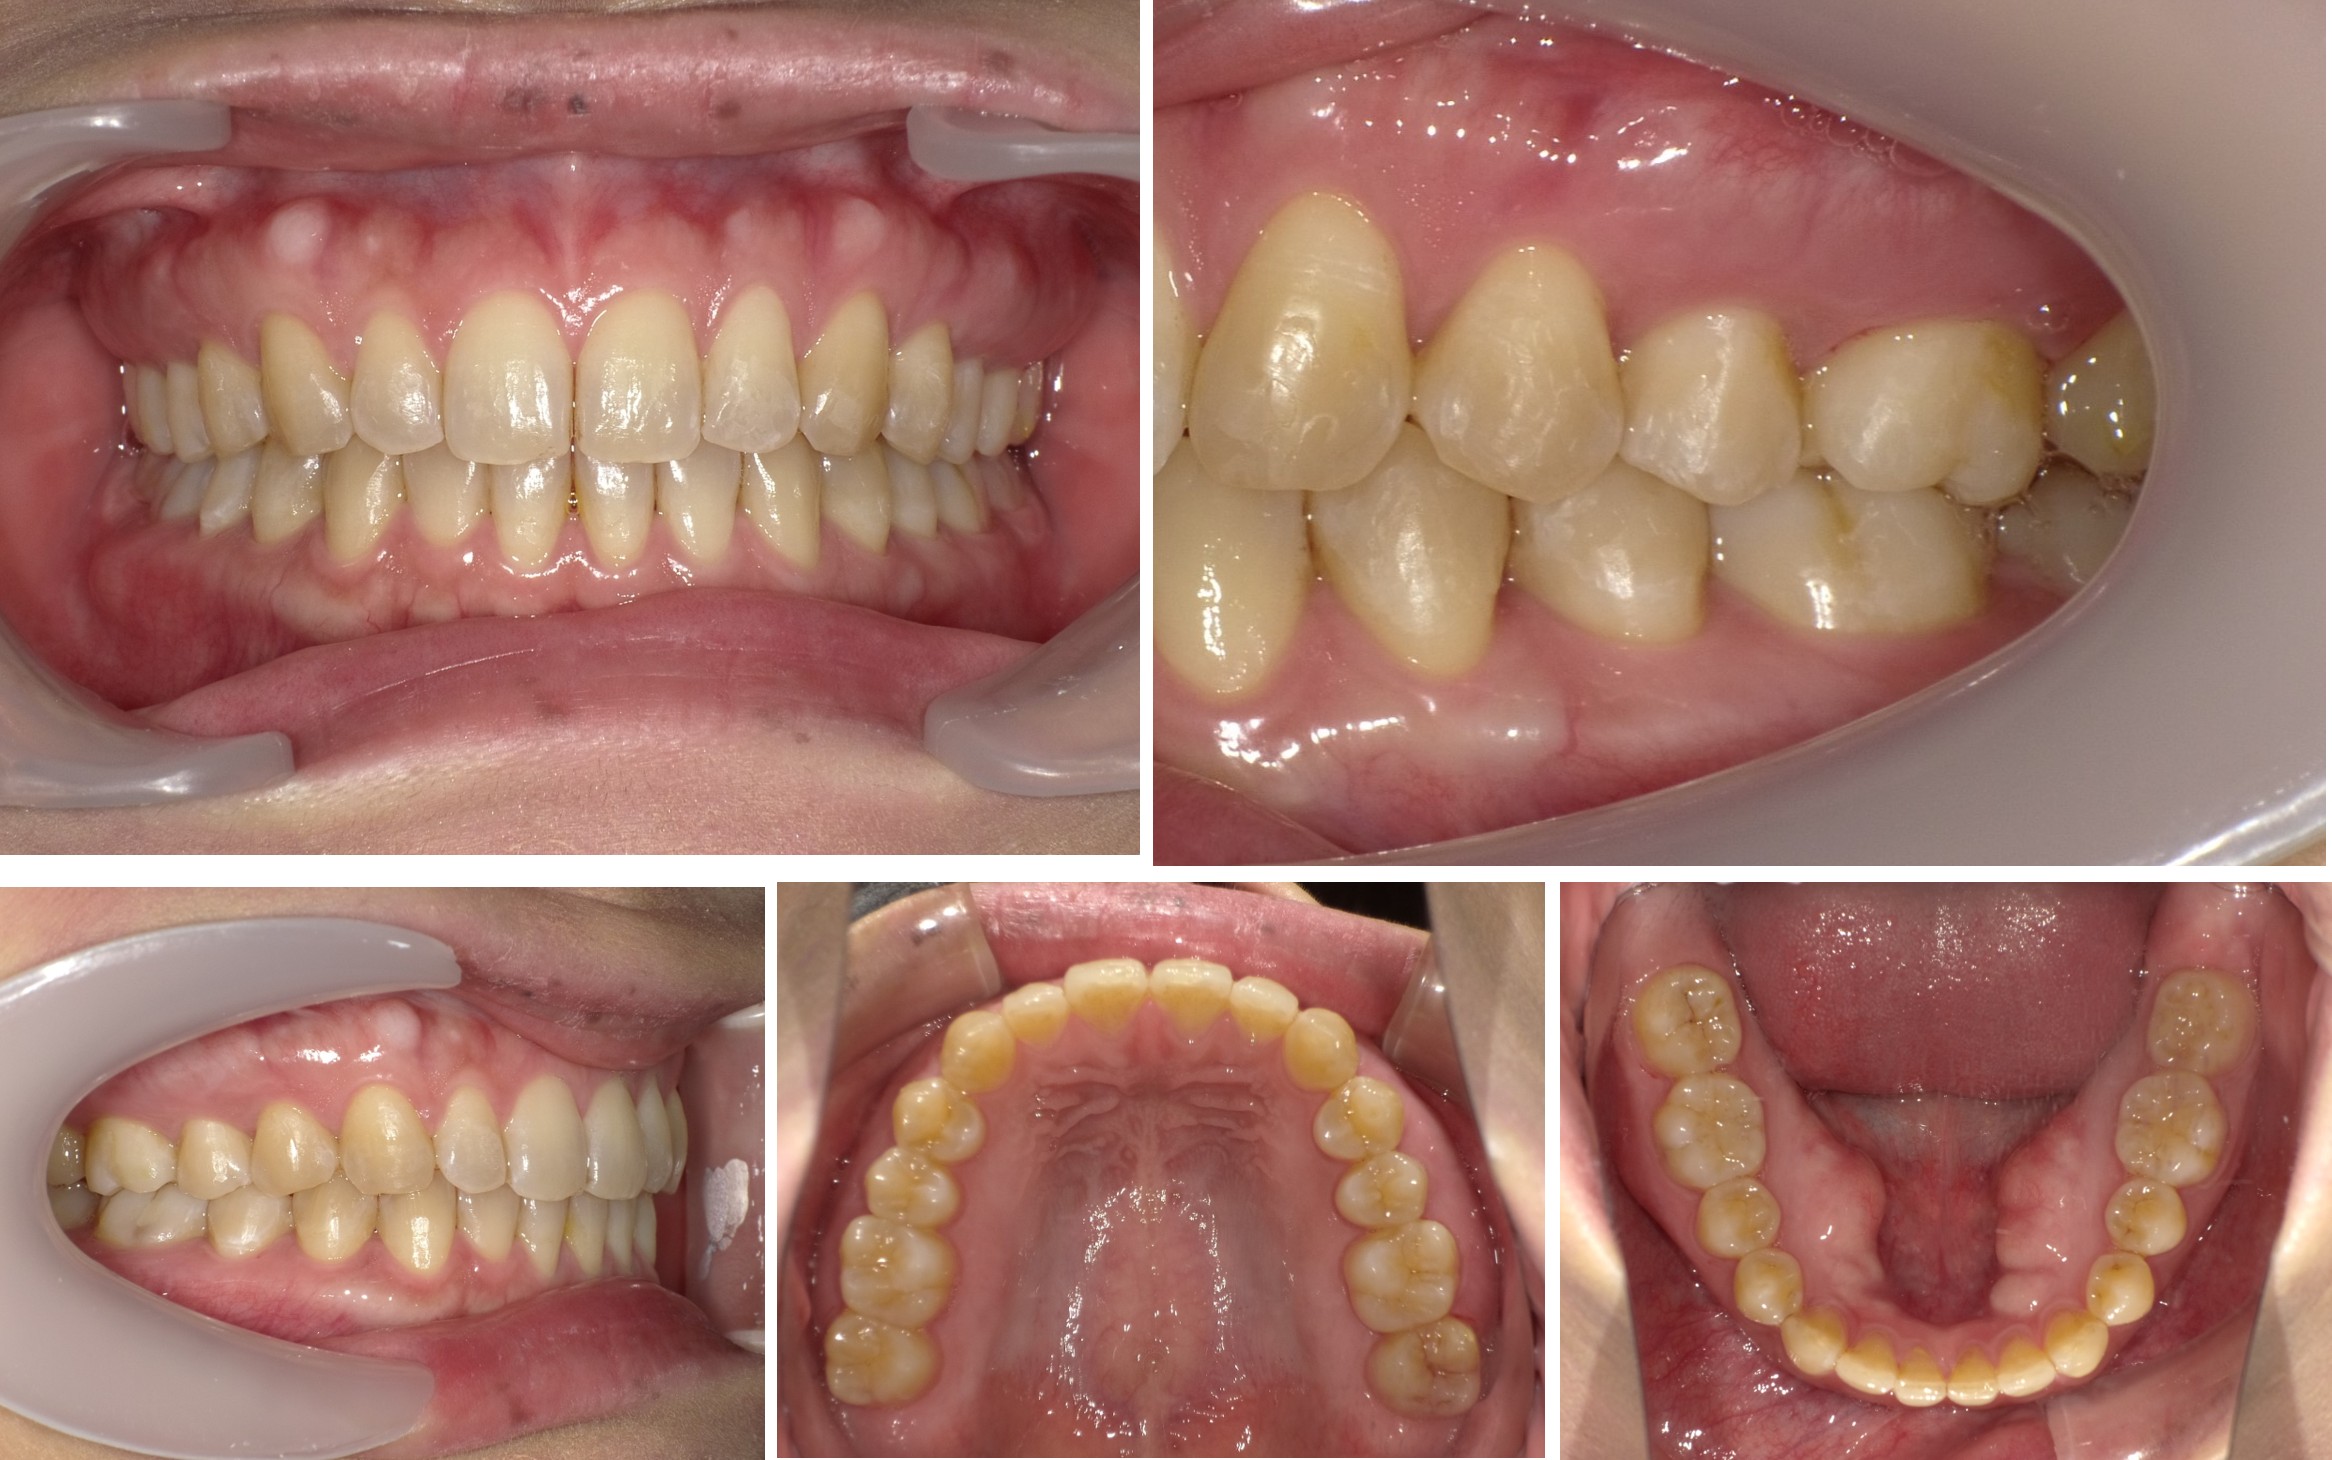

歯列矯正治療前の分析・診断

検査の際のレントゲン写真、お口の中の写真、お顔の写真をもとに分析・診断を行い、歯列矯正治療の計画を作成していきます。

歯列矯正治療のビフォーアフター、治療にかかった期間や来院回数について解説いたします。

治療症例